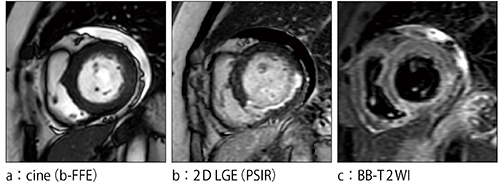

症例5:下壁心筋梗塞

稼働間もない時点ですでに,3T装置と遜色ないパフォーマンスを発揮し,多くのメリットをもたらしているProdiva 1.5T CXであるが,聖隷三方原病院では,今後その能力を十分に生かせるよう,検査枠などの見直しなども検討している。高橋医長は,「セッティングを含めた検査スループットが良いので,骨転移症例の探索などに全身body DWIを積極的に使用できます。全身body DWIは,血液内科をはじめ,悪性腫瘍を扱う診療科の医師からも有用性が認められており,今後は検査枠を設けて施行していくことを検討しています」と述べる。高橋医長は,例えば悪性リンパ腫において,まずFDG-PET検査できちんと診断した上で,フォローアップを全身body DWIでも行うことで,その後のFDG-PET検査を減らすことも可能になると考えている。心臓MRIについても,現時点でもまったく問題なく撮像できているが,今後のバージョンアップでT1マッピングが可能となる予定で,よりいっそう有用な検査になることに期待している。